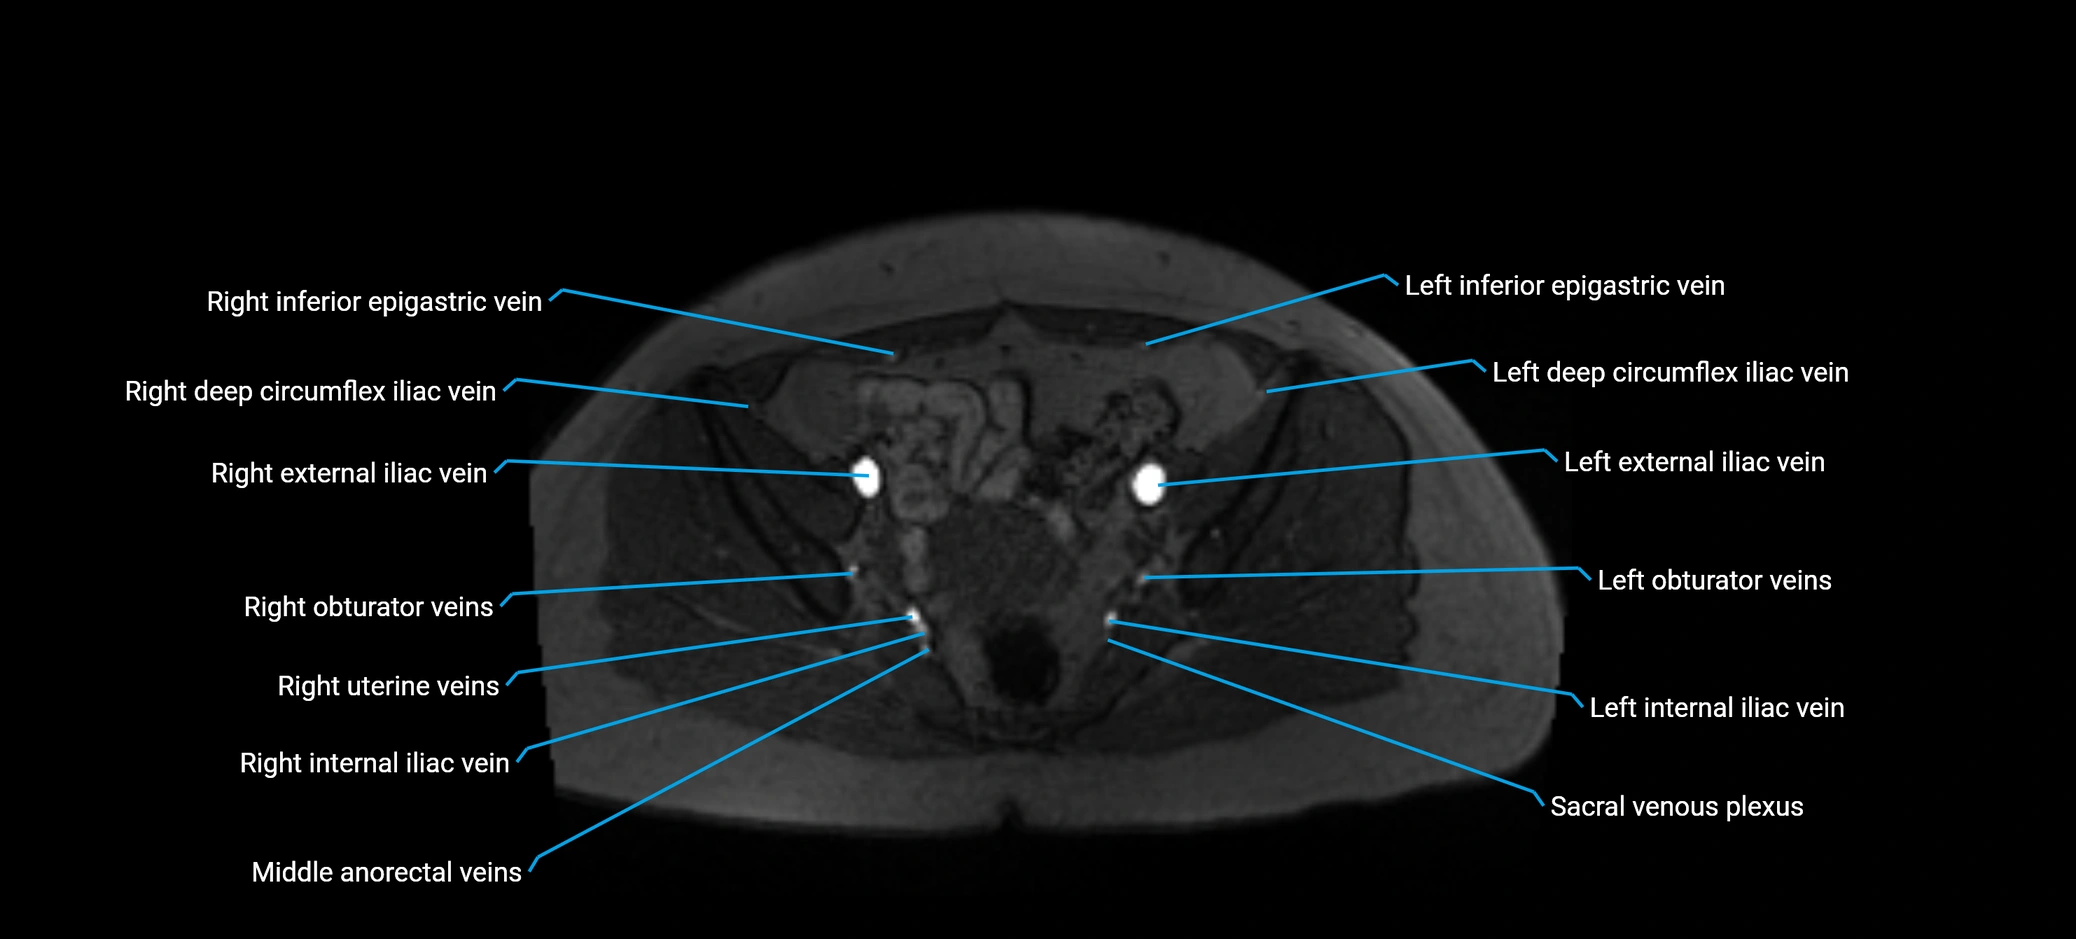

image